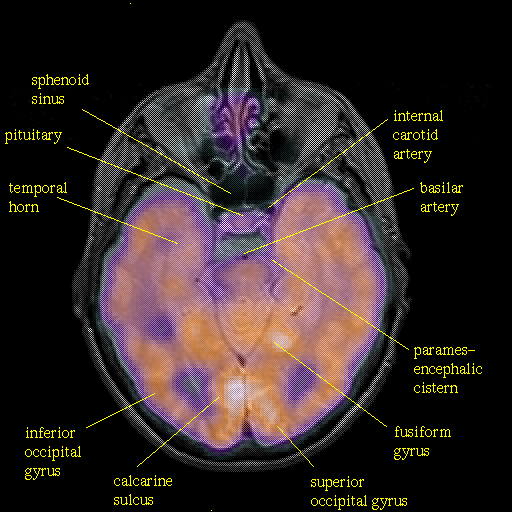

overlay : Slice 20

Slice 20